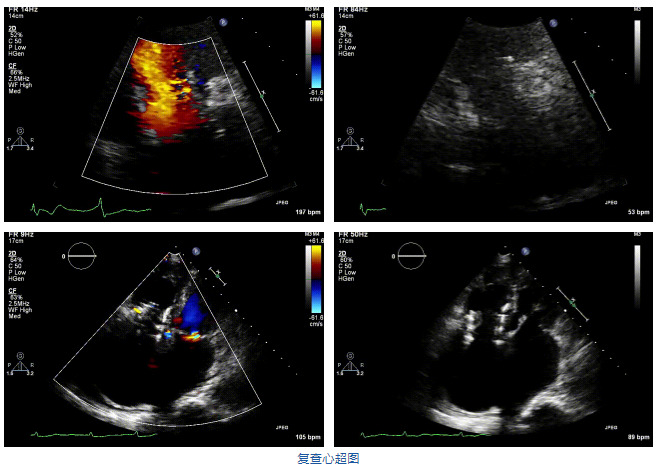

2021年12月7日,復旦大學附屬中山醫(yī)院葛均波院士團隊完成的首批兩例LuX-Valve Plus經(jīng)血管三尖瓣置換患者順利出院,從患者入院至出院僅歷時一周時間,出院時患者狀態(tài)恢復良好,復查心超三尖瓣無反流。

結(jié)合術前CT評估結(jié)果,葛均波院士團隊最終決定選用LuX-Valve Plus 50mm和55mm兩種型號的瓣膜,并于2021年11月30日順利完成LuX-Valve Plus經(jīng)血管三尖瓣置換術,手術室即刻拔除氣管插管,術后第二天轉(zhuǎn)出心內(nèi)科監(jiān)護室,下床活動。術后患者三尖瓣反流癥狀得到顯著改善,復查心超結(jié)果顯示人工三尖瓣瓣膜支架固定穩(wěn)定,瓣葉關閉形態(tài)未見異常,未見明顯反流。

在本次救治性臨床研究中,治療的兩例患者病因不同,解剖結(jié)構(gòu)復雜,均為極重度三尖瓣反流,手術最終都順利植入了LuX-Valve Plus三尖瓣人工瓣膜。術后超聲顯示瓣膜支架固定穩(wěn)定,反流癥狀顯著改善,取得了良好臨床治療效果。